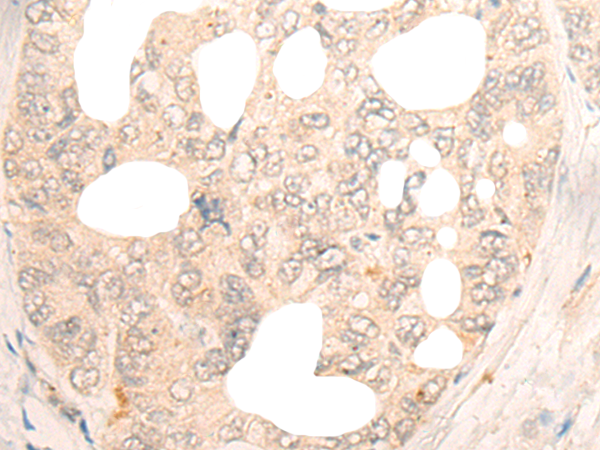

The image is immunohistochemistry of paraffin-embedded Human gastric cancer tissue using 47023(DBX2 Antibody) at dilution 1/20. (Original magnification: ?00)